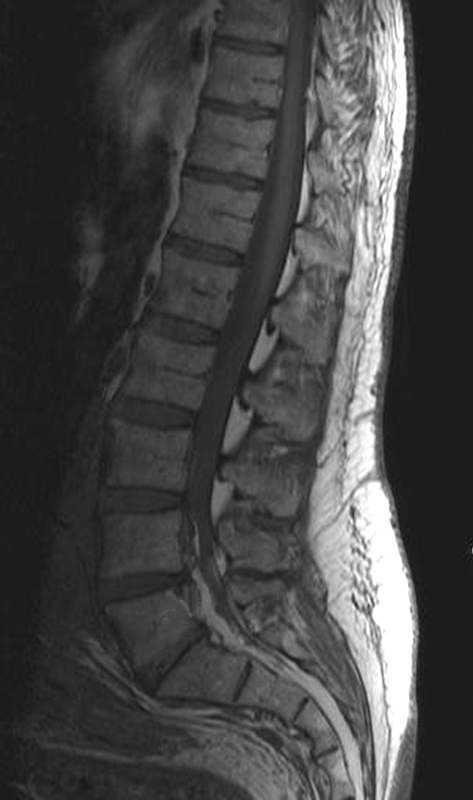

Fig. 2. Resonancia magnética ponderada en T2 (A) sagital línea media y (B) parasagital. En el espacio epidural anterior (A) y en los forámenes de conjunción (B) se aprecian estructuras vasculares con aspecto serpinginoso y arrosariado (flechas).